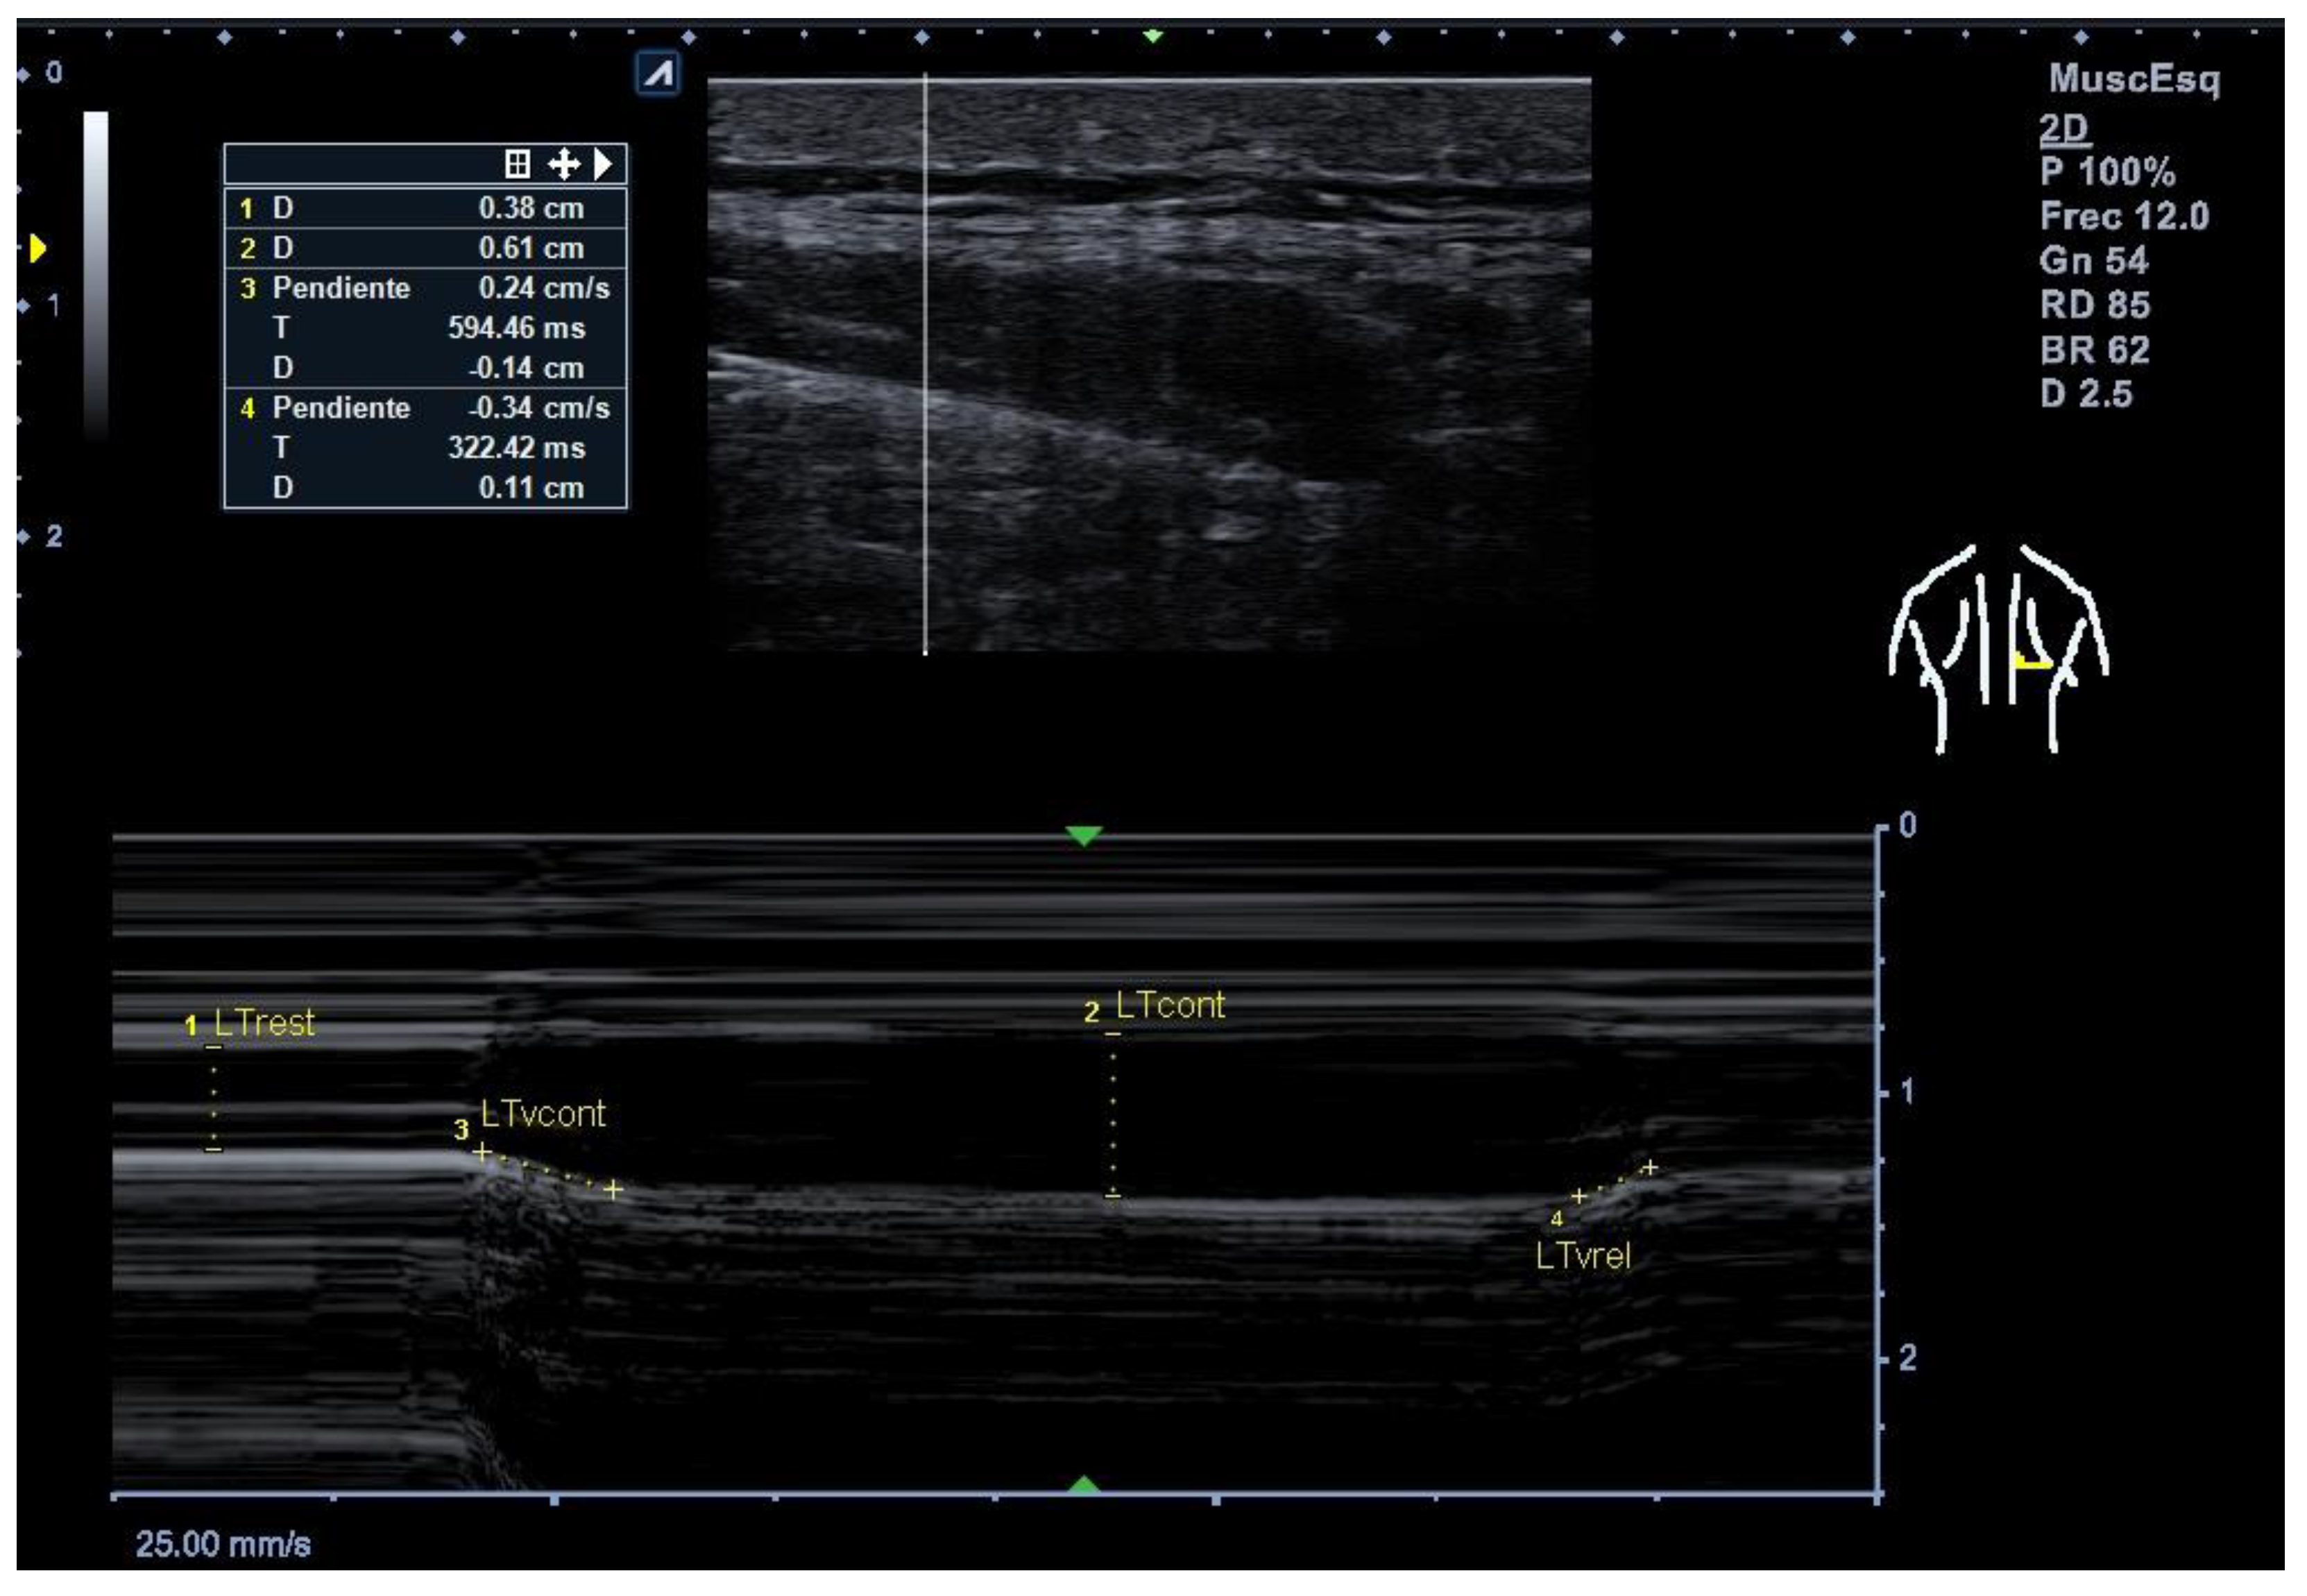

2.8. Thickness Measurements, Velocity of Contraction and Relaxation (M-Mode)

Figure 1. Example of M-mode ultrasound measurement of the lower trapezius muscle. LTrest = lower trapezius thickness at rest (cm); LTcont = lower trapezius thickness at contraction (cm); LTvcont = contraction velocity (cm/s); LTvrel = relaxation velocity (cm/s). The vertical and oblique dotted lines indicate the points used for thickness and velocity calculations. Scale: 25 mm/s (horizontal), 1 cm (vertical).